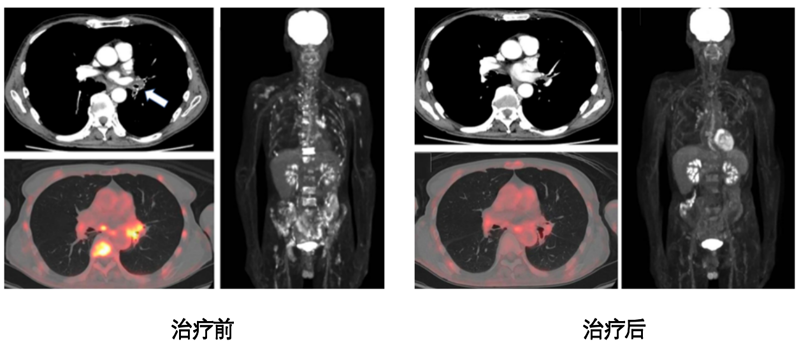

在启动治疗后的24周,患者完成整个治疗疗程,研究组通过影像评估了患者治疗前后骨转移灶的变化。

通过PET-CT检测,我们发现患者的脊柱、双侧股骨及肱骨的转移灶均得到有效控制,患者实现了完全缓解。

本病例为1位罕见的复发性肺鳞癌伴骨髓转移患者,经过以新抗原DC疫苗为核心的综合治疗后,成功实现了骨转移灶的完全缓解。该案例不仅凸显了肺鳞癌骨髓转移的临床罕见性与治疗复杂性,也为个体化免疫治疗在实体瘤转移管理中的应用提供了有力依据。